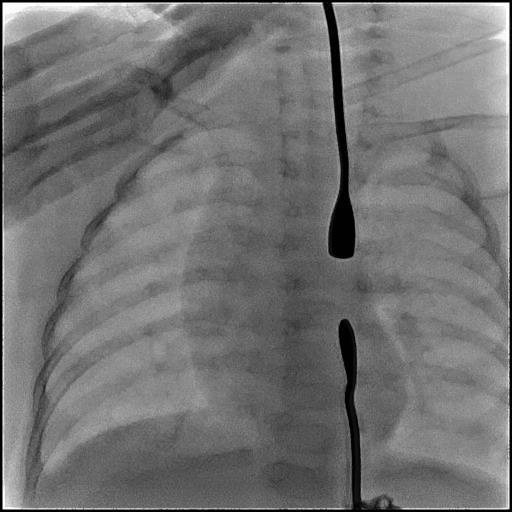

近日,在上海交通大学医学院附属新华医院(以下简称“新华医院”),儿普外科专家为小仁仁进行了食道重建手术,在小小的胸部仅打了3个5mm的小孔,将原本是个“死胡同”的食道,成功地“解锁”了。

先天性食道闭锁是新生儿期严重消化道畸形,食道上下没有相连,一旦喂奶,将全部进入肺部,如不手术,患儿将在很短的时间内因营养不良和肺炎双重打击迅速死亡。胸腔镜下食管闭锁手术被称为新生儿外科手术领域皇冠上的明珠,总体治疗难度高,是国际上公认的体现新生儿外科总体水平的标志性疾病。而仁仁所患的食道闭锁I型又是其中最罕见、最严重的一种。他的食管近远端距离约达4.8cm,属于长段缺失型食管闭锁。由于仁仁年龄小,手术难度极大,当地医院就先为仁仁做了胃造瘘手术。手术后经胃造瘘喂养。于是,贡噶曲则抱着仁仁辗转成都等地,开始了千里求医之路。经病友介绍,贡噶曲则通过互联网找到了新华医院儿普外科主任王俊。

“患儿手术时只有5公斤多一点,微创操作本身视野小,新生儿组织结构脆弱,所以对操作精细度要求很高。”新华医院儿普外科主任王俊介绍,尽管手术难度大,但胸腔镜微创的手术方案,避免了传统开胸手术带来的巨大创伤和后遗症,更利于仁仁的恢复。除了外科手术,先天性食道闭锁治疗其实更是一个多学科联合诊治的过程。

“比如食道闭锁的孩子往往在气道方面也会有一些问题,所以要早发现,进行一些功能上的训练。”王俊说,像仁仁这样的孩子因为食道闭锁没法吃东西,新生儿天生的吸吮反射几周后就会消失,“到时候他就不会吞咽了,所以说孩子一到医院我们就给他做了一个吞咽反射的训练。”此外,还要定期对仁仁进行食道内应力延长,让食道近远端距离尽早符合手术条件。最终,在多学科的保驾护航下,王俊在细若棉线的食道上穿针引线,完成食管重建。整个手术仅耗时1小时40分钟,手术出血仅为2ml。